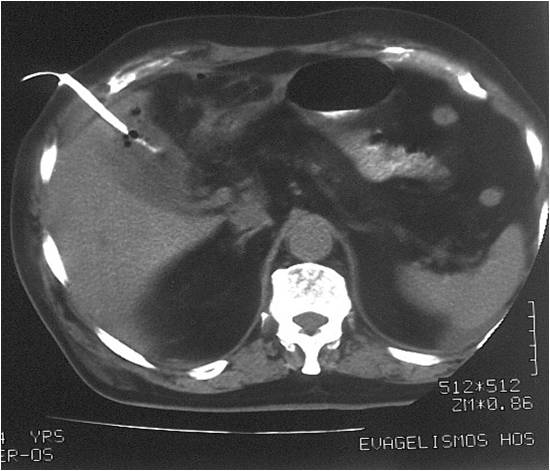

- Right sub diaphragmatic abscess post right hemicolectomy

- Successful drainage